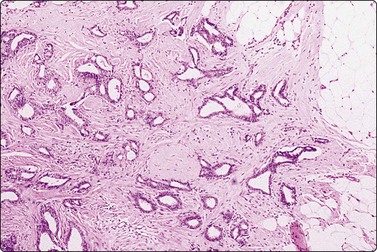

image image

Fig. 7.2 Non-neoplastic glandular breast tissue and low-grade duct carcinoma

Low-power view; (A) Bimodal population of epithelial sheets and single bipolar nuclei of non-neoplastic glandular breast tissue; (B) Single population of epithelial cells in low-grade carcinoma (MGG, LP).

Fig. 7.3 Non-neoplastic glandular breast tissue and low-grade duct carcinoma

High-power view, air-dried smears; (A) Non-neoplastic glandular breast tissue; (B) Low-grade duct carcinoma. Note single bipolar nuclei in A, and absence of bipolar nuclei, relatively mild nuclear atypia and some loss of cohesion of malignant cells in B (MGG, HP).

Fig. 7.4 Non-neoplastic glandular breast tissue and low-grade duct carcinoma

High-power view, Pap-stained smears; (A) Bimodal population in smear from non-neoplastic breast; (B) Single and clustered cells in low-grade carcinoma; some single cells probably stromal (Pap, HP).

A comparison between the basic benign pattern (non-neoplastic glandular tissue) and the most common malignant pattern (low-grade carcinoma of no special type) in FNB of breast lesions is given in Table 7.2 (Figs 7.2-7.4).

Table 7.2 Comparison of the benign pattern and low-grade carcinoma in FNB smears

Non-neoplastic breast tissue (Figs 7.2A, 7.3A and 7.4A) Low-grade carcinoma NOS (Figs 7.2B, 7.3B and 7.4B)

1. Overall low cell yield 1. Variable but higher cell yield

2. Sheets and aggregates of cohesive, small, uniform cells 2. Irregular clusters of less cohesive, small, mildly irregular cells

3. Small rounded nuclei, bland chromatin, some overlapping 3. Slightly larger and darker nuclei, relatively bland chromatin

4. Myoepithelial cell nuclei among epithelial cells 4. Myoepithelial cell nuclei not seen

5. Variable numbers of single, bare, bipolar nuclei scattered in the background 5. Single cells, most with some cytoplasm, identical to those forming clusters; no bare bipolar nuclei